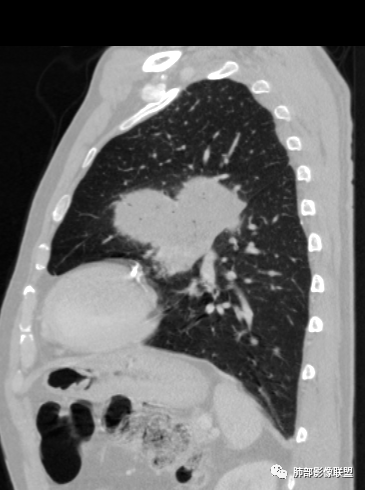

左肺上叶大肿块,膨胀性生长,边界清,密度较低,见部分坏死区,强化弱,肿块见支气管充气V扩张征,分布僵直,枯树枝特点,另一个重要特点血管造影征,淋巴瘤,肿块长轴与胸膜平行,与隐球菌鉴别,隐球荚膜抗原检查,明确诊断经皮肺穿刺。另胸膜钙化(问诊既往有无患胸膜炎病史)。

老年男性,糖尿病病史,消瘦、乏力三个月,影像表现左肺上叶胸膜下团块,有一定张力,内部疏松,可见支气管影及坏死区,增强病灶边缘环形强化,内部未见强化,考虑炎性肉芽肿病变,隐球?奴卡?放线菌?鉴别淋巴瘤。

左肺上叶胸膜下肿块,宽基底与胸膜相连,跨叶裂,边缘清晰膨隆,其内支气管充气,部分扩张、僵直,无明显强化,血管造影征,考虑淋巴瘤,鉴别腺癌

左肺胸膜下巨大占位,跨叶裂,宽基底与胸膜相连,胸膜钙化,平扫密度较低,强化不明显,可见内部血管显影,支气管充气征和扩张,考虑为恶性,倾向于淋巴瘤

大肿块,边缘光滑,深分叶

近端支气管堵塞、推移为主

部分类似于脐凹征

内部支气管扩张

肺动脉推移为主,边缘部分进入

大肿块、表面光滑但深分叶,肺门侧支气管堵塞

1)部位:周围型或中央型软组织肿块,以周围型为多见,且肿瘤多位于肺上叶。如本例:该肿瘤位于左肺上叶。

2)大小及形态:由于本病恶性程度高,早期症状不明显,发现时肿块均较大。如本例病变巨大。

3)肿块边界和边缘:多较清楚,呈圆形、类圆形,且由于肿块生长速度不均匀,可见分叶,毛刺少见。有报道肿块周围毛玻璃影是多形性癌特征表现。

4)密度:肿块平扫为软组织密度,由于体积较大,内部常见大片状坏死,可出现不规则厚壁空洞或坏死内多发无壁小空洞,坏死多不均匀:坏死灶内可见如柳絮样的斑片样强化灶,坏死边缘与非坏死区分界不清本例坏死较明显,密度不均匀。

5)肿瘤强化方式:肺部恶性肿瘤强化程度与其血供丰富程度相关,血供丰富多强化明显,反之则较差。由于PSC 周边实性部分富血供及内部黏液变性、坏死,增强后肿块多数呈轻-中度边缘环形强化或不均匀小斑片状强化。国外学者对照病理发现肿瘤细胞或胶原组织增强扫描时强化,无强化的低密度区代表了黏液样变性区和出血坏死区。